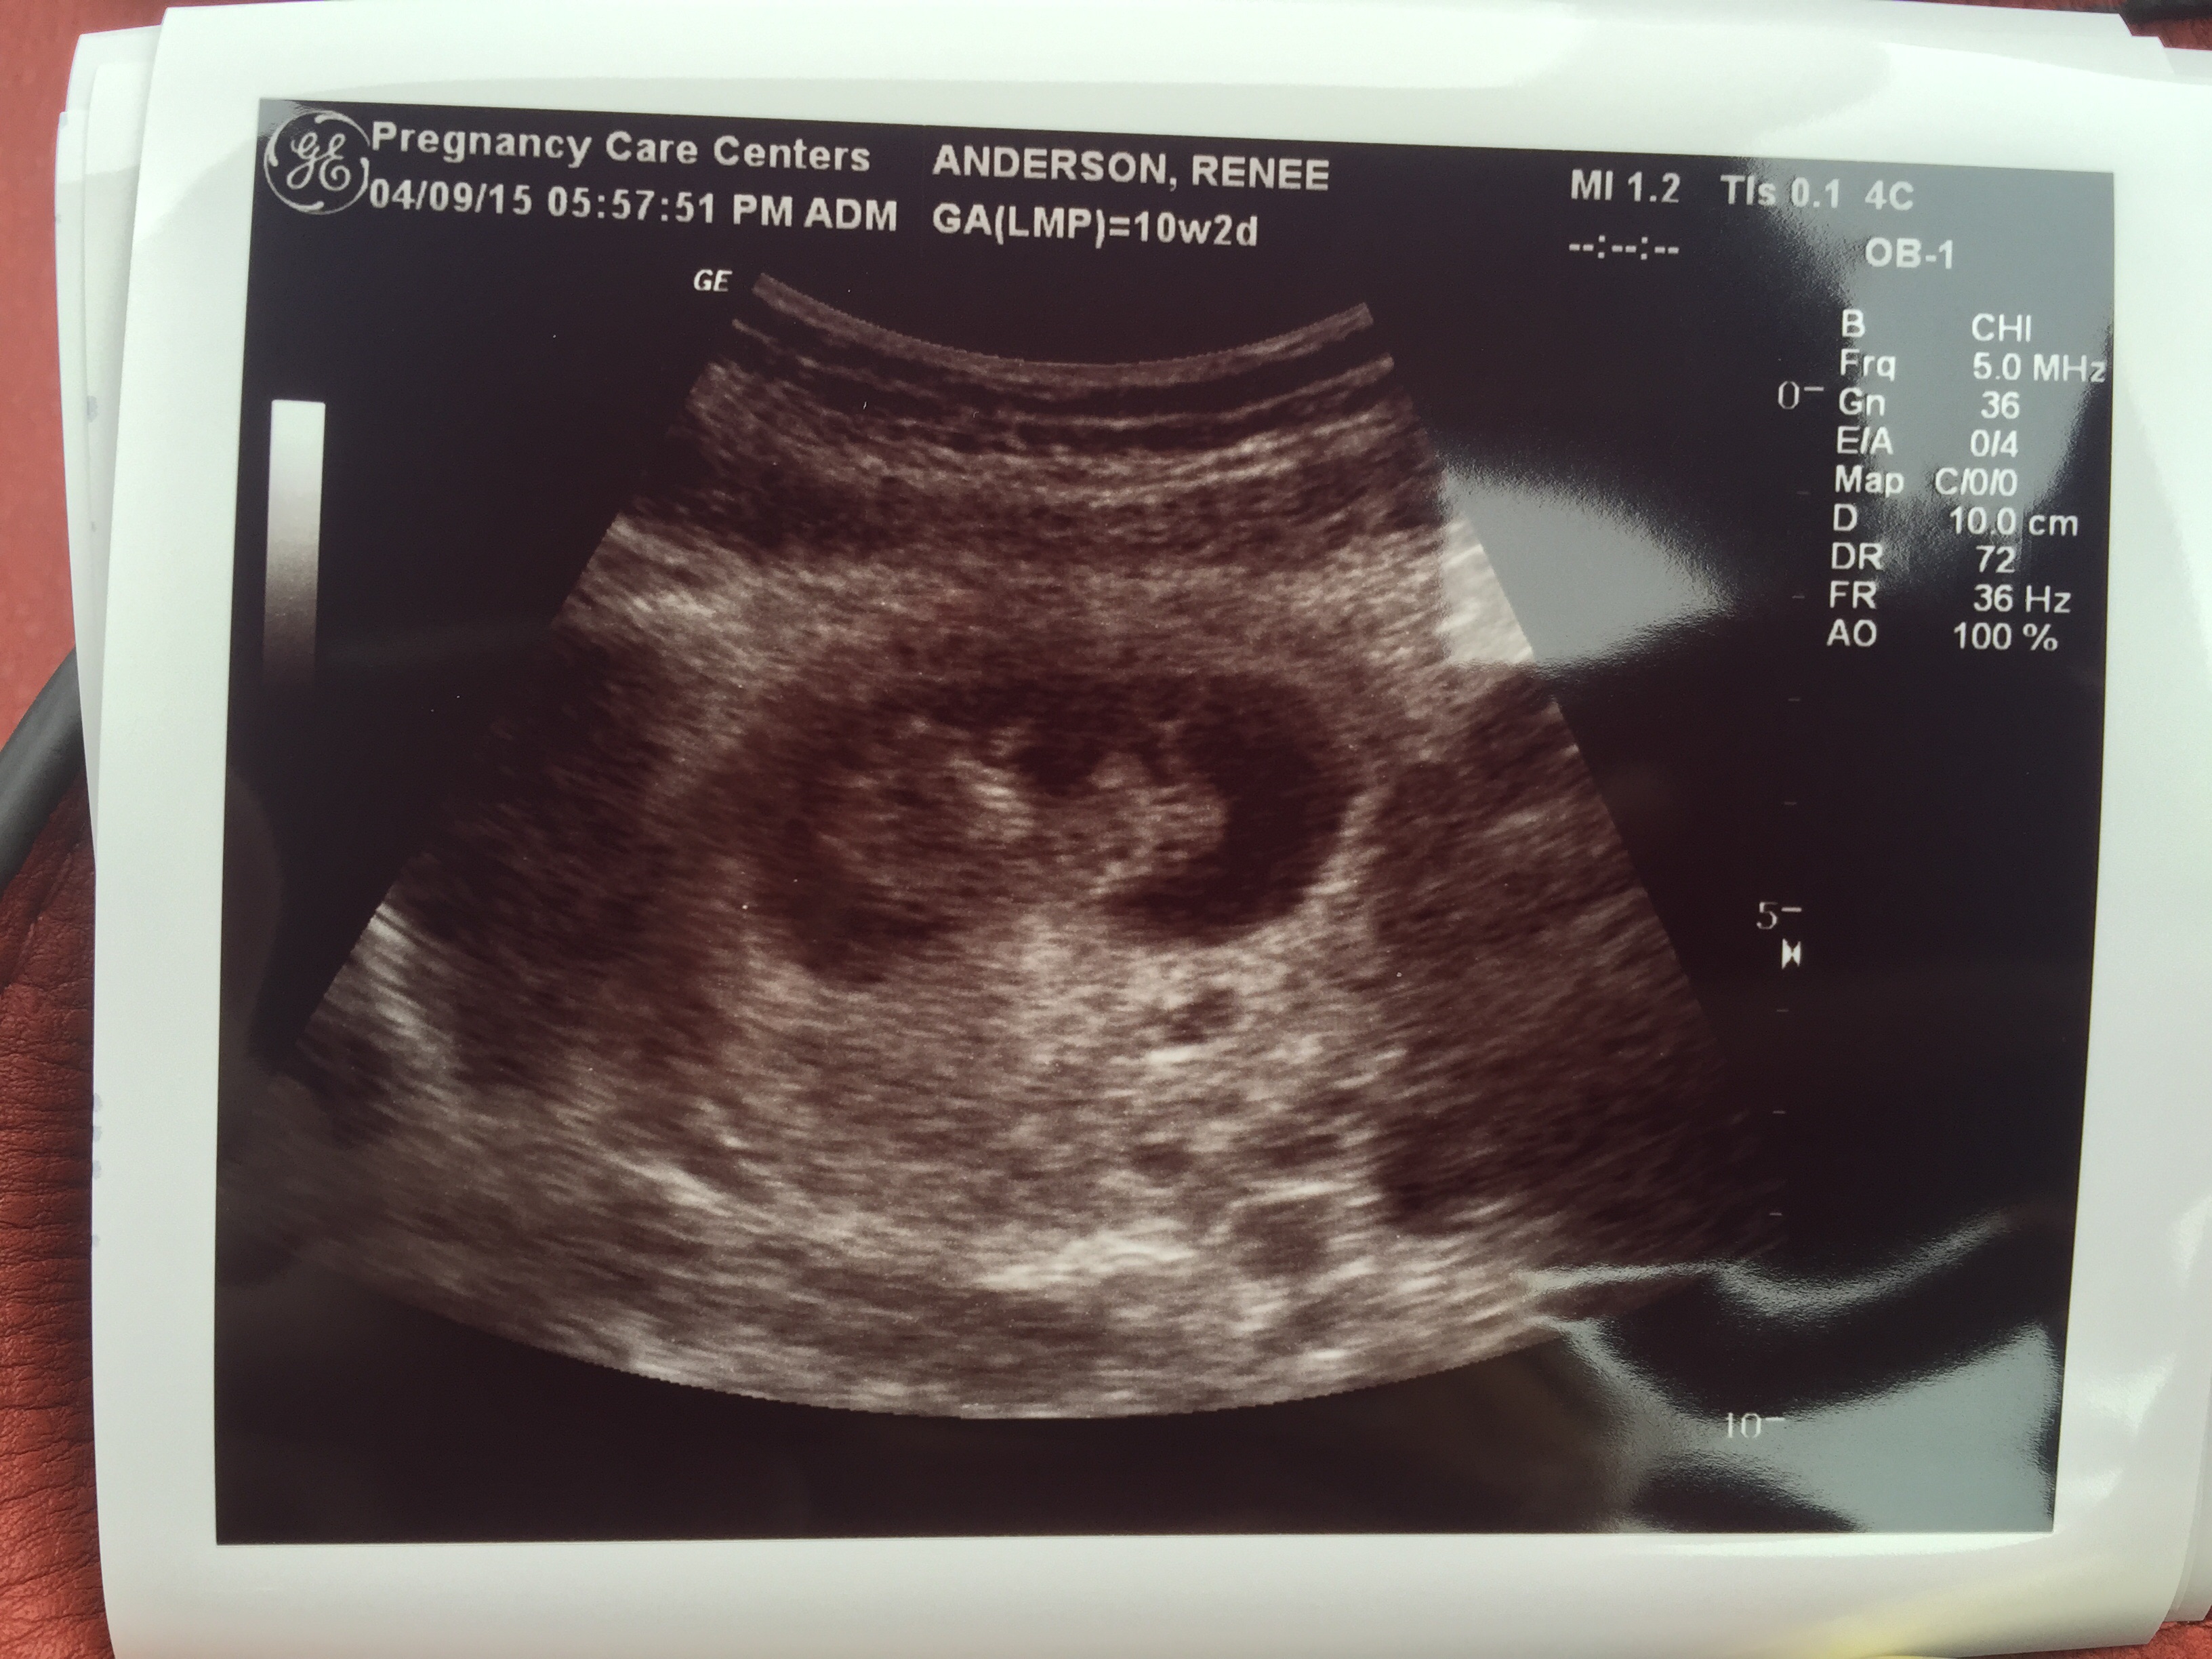

Originally thought I was due early November and found out yesterday I'm a week ahead and due late October! My birth month too

image.jpg